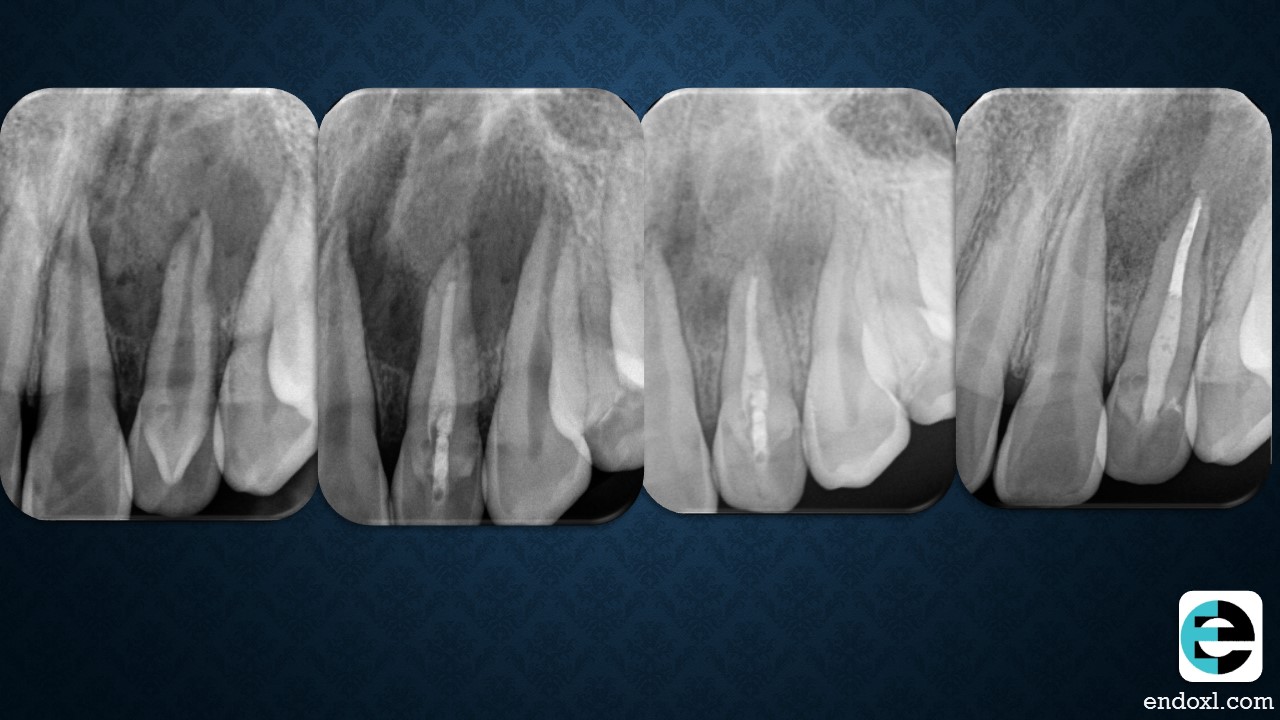

Intriguing dental journey Rajiv Patel. Following the 15 yom recovery with keen interest. Your dedication to multiple visits and strategic treatments is commendable.